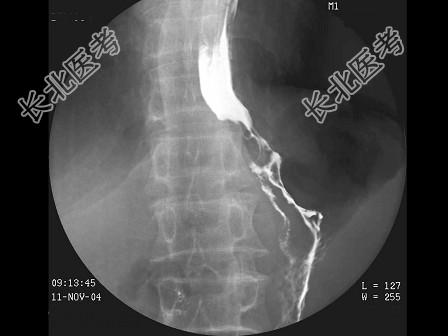

- 单项选择题男,59岁, 进行性吞咽困难半年,结合图像, 最可能的诊断为 ( )

D、食管癌

E、贲门癌侵及胃底、食管下段